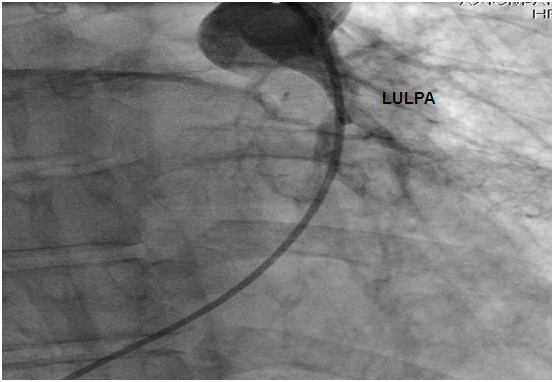

Figure 5: Hypotrophic LULPA with no veinous drainage. LULPA: Left Upper Lobar Pulmonary Artery.

Discussion